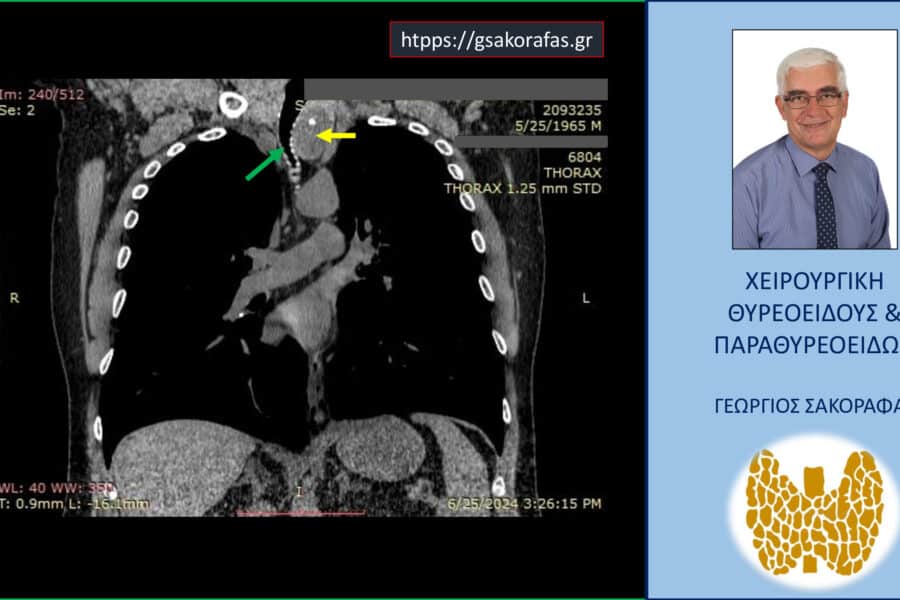

ΒρογχοκήληΚαταδυόμενη Βρογχοκήλη Καταδυόμενη βρογχοκήλη με εξαιρετικά μεγάλο βάθος κατάδυσης στο θώρακα σε υπερήλικα ασθενή – αφαίρεση μέσω της τραχηλικής τομής (Εικόνες) Καταδυόμενη βρογχοκήλη με εξαιρετικά μεγάλο βάθος κατάδυσης στο θώρακα σε υπερήλικα ασθενή Παρουσίαση ασθενούς…George Sakorafas6 Οκτωβρίου 2025